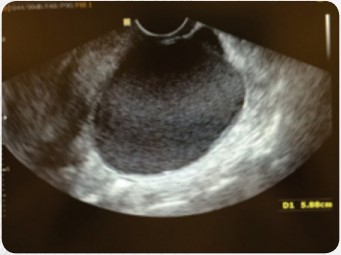

Um implante superficial atinge a face externa dos ovários, provoca uma retração para o interior do mesmo e forma cistos. O tamanho dos cistos é variável e causa alterações da anatomia destes órgãos. O diagnóstico é fácil, feito pelo ultrassom.

O tratamento quase sempre é cirúrgico por videolaparoscopia. O rigor da técnica cirúrgica utilizada é fundamental para que se evite o prejuízo da reserva ovariana, caso contrário, junto com o tecido do cisto, poderá ser retirado também tecido ovariano com óvulos de boa qualidade podendo levar até à falência ovariana precoce. O cisto pode estar associado a endometriose de outros órgãos formando aderências. Muitas vezes a paciente não tem sintomas e o diagnóstico pode ocorrer em um exame ginecológico de rotina. A indicação cirúrgica vai depender do tamanho do cisto entre outras variáveis.